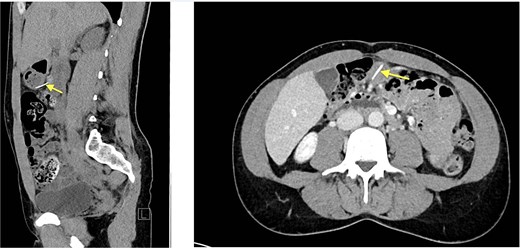

Repeat CT (05.05.2024) demonstrated the wire had migrated, now traversing the posterior gastric wall into the mesentery near the hepatic flexure. New gas collections in the Morrison pouch and right subdiaphragmatic space were noted [11].

Given persistent pain and fever, a second-look laparoscopy was undertaken. Access to the lesser sac via the gastrocolic ligament revealed the metallic wire (Fig. 2), embedded near the pyloric region. It was successfully extracted without mucosal rupture or abscess formation.